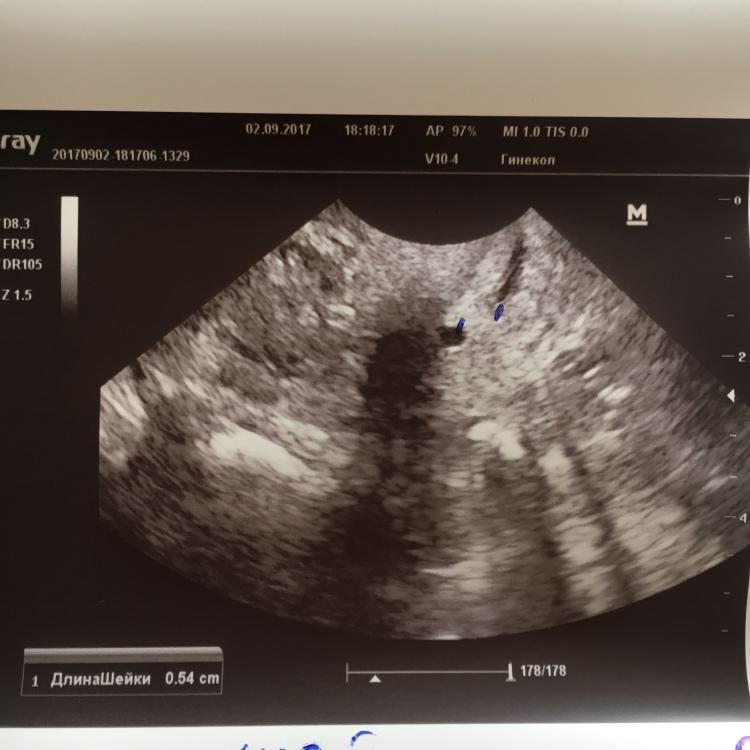

Прикрепляю фото с УЗИ, может кто-то разбирается и посмотрит, похоже на полип или нет?

На фото нет признаков полипа, по крайней мере при таком расширении ЦК нельзя о нем говорить. поэтому врач абсолютно права, что намеревается провести контроль после менструации.

К сожалению, снимок мог быть более четкий, шейка не совсем точно выведена, вернее врач переключил режим в контрастный, возможно, поэтому сложно разобрать. Но если на кресле врач не видит полипа, то абсолютно точно, есть достаточно времени, чтобы подождать контрольного обследования.